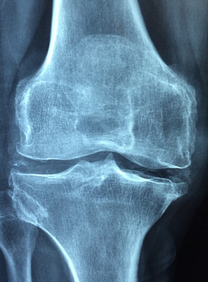

무릎 연골은 무릎 관절의 움직임을 도와주는 부드러운 조직입니다. 무릎 연골은 무릎 관절에서 마찰과 충격을 완화하여 뼈와 뼈가 부드럽게 움직일 수 있도록 도와줍니다. 무릎 연골은 건강한 상태에서는 매끄럽고 탄력적이며, 충격을 흡수할 수 있습니다. 하지만 연령과 함께 연골은 마모되며, 외상이나 질병으로 인해 손상을 입을 수도 있습니다. 무릎 연골손상은 무릎 통증, 불편감, 굴곡 제한 등을 유발할 수 있으며, 중증의 경우 수술이 필요할 수 있습니다. 따라서, 건강한 식습관과 적절한 운동, 적절한 보호장비 사용 등으로 무릎 연골 건강을 유지하는 것이 중요합니다.

무릎 연골에 좋은 식품에 대해 알아보겠습니다. 무릎 연골은 우리 몸의 관절을 보호하고 쿠션 역할을 하는 중요한 조직입니다. 하지만 나이가 들거나 과도한 운동으로 인해 무릎 연골이 손상되면 통증이나 염증이 발생할 수 있습니다. 이런 경우에는 무릎 연골을 재생하거나 보호할 수 있는 식품을 섭취하는 것이 좋습니다.